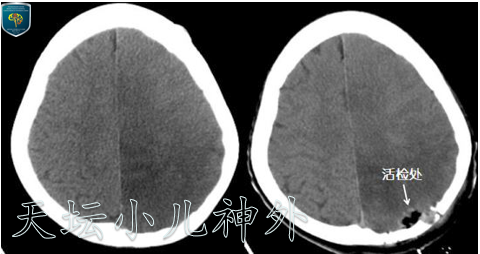

历经三年就医,内科外科用尽各种方法,病情逐渐恶化,诊断都是一头雾水,何谈治疗。家长抱着最后一线希望来到北京天坛医院,鉴于病情复杂,我们决定对表浅位置的病变施行开窗活检术,尽量多取材,以明确病理性质。患儿于2020年08月18日在我院全麻下行左顶开颅病变开窗活检术,显微镜下切除病变大小约10×10×10mm,术后病理回报提示:混合性神经元胶质肿瘤(WHOⅡ级),经过三年的辗转,终于明确病变的性质与级别。

图4开窗活检前后CT